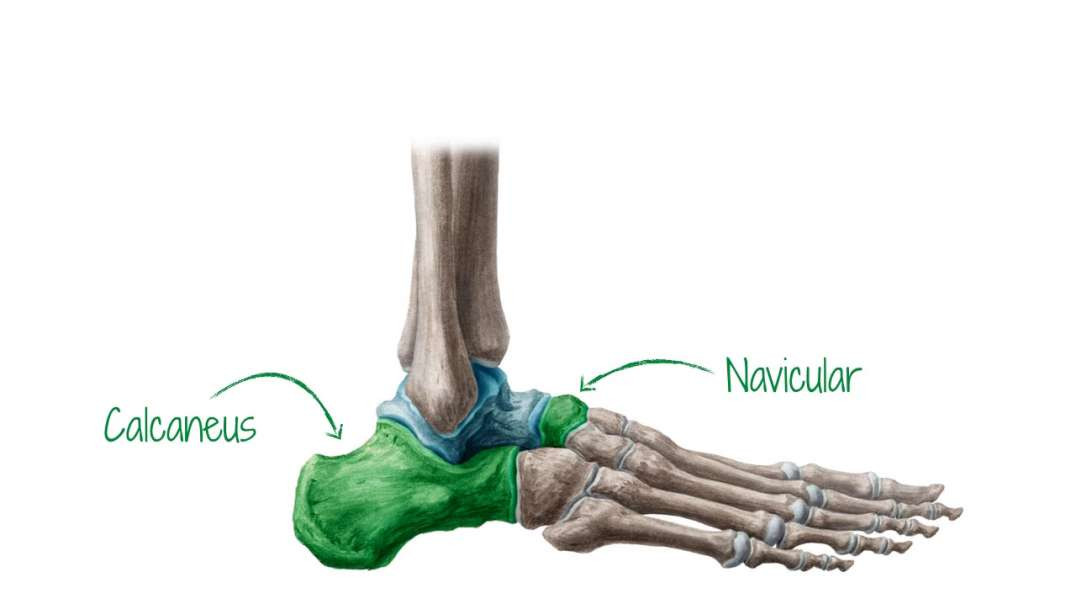

Joints and blood supply of talus

Joints and blood supply of talus kenhub